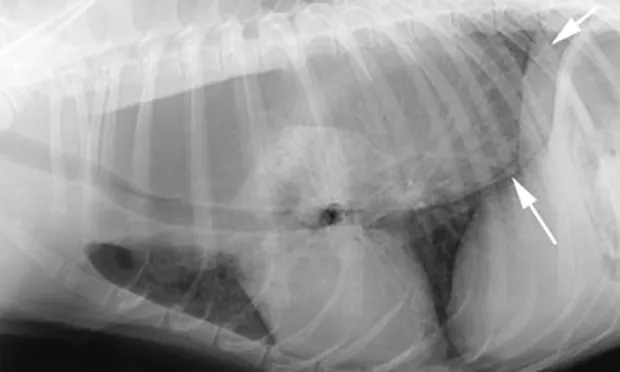

Right lateral radiograph from a dog with left atrial enlargement (A). Note the dorsal deviation of the carina secondary to severe left atrial enlargement (arrow). In a radiograph obtained from a dog with enlargement of the central tracheobronchial lymph node (B), ventral deviation of the carina can be seen (arrow).